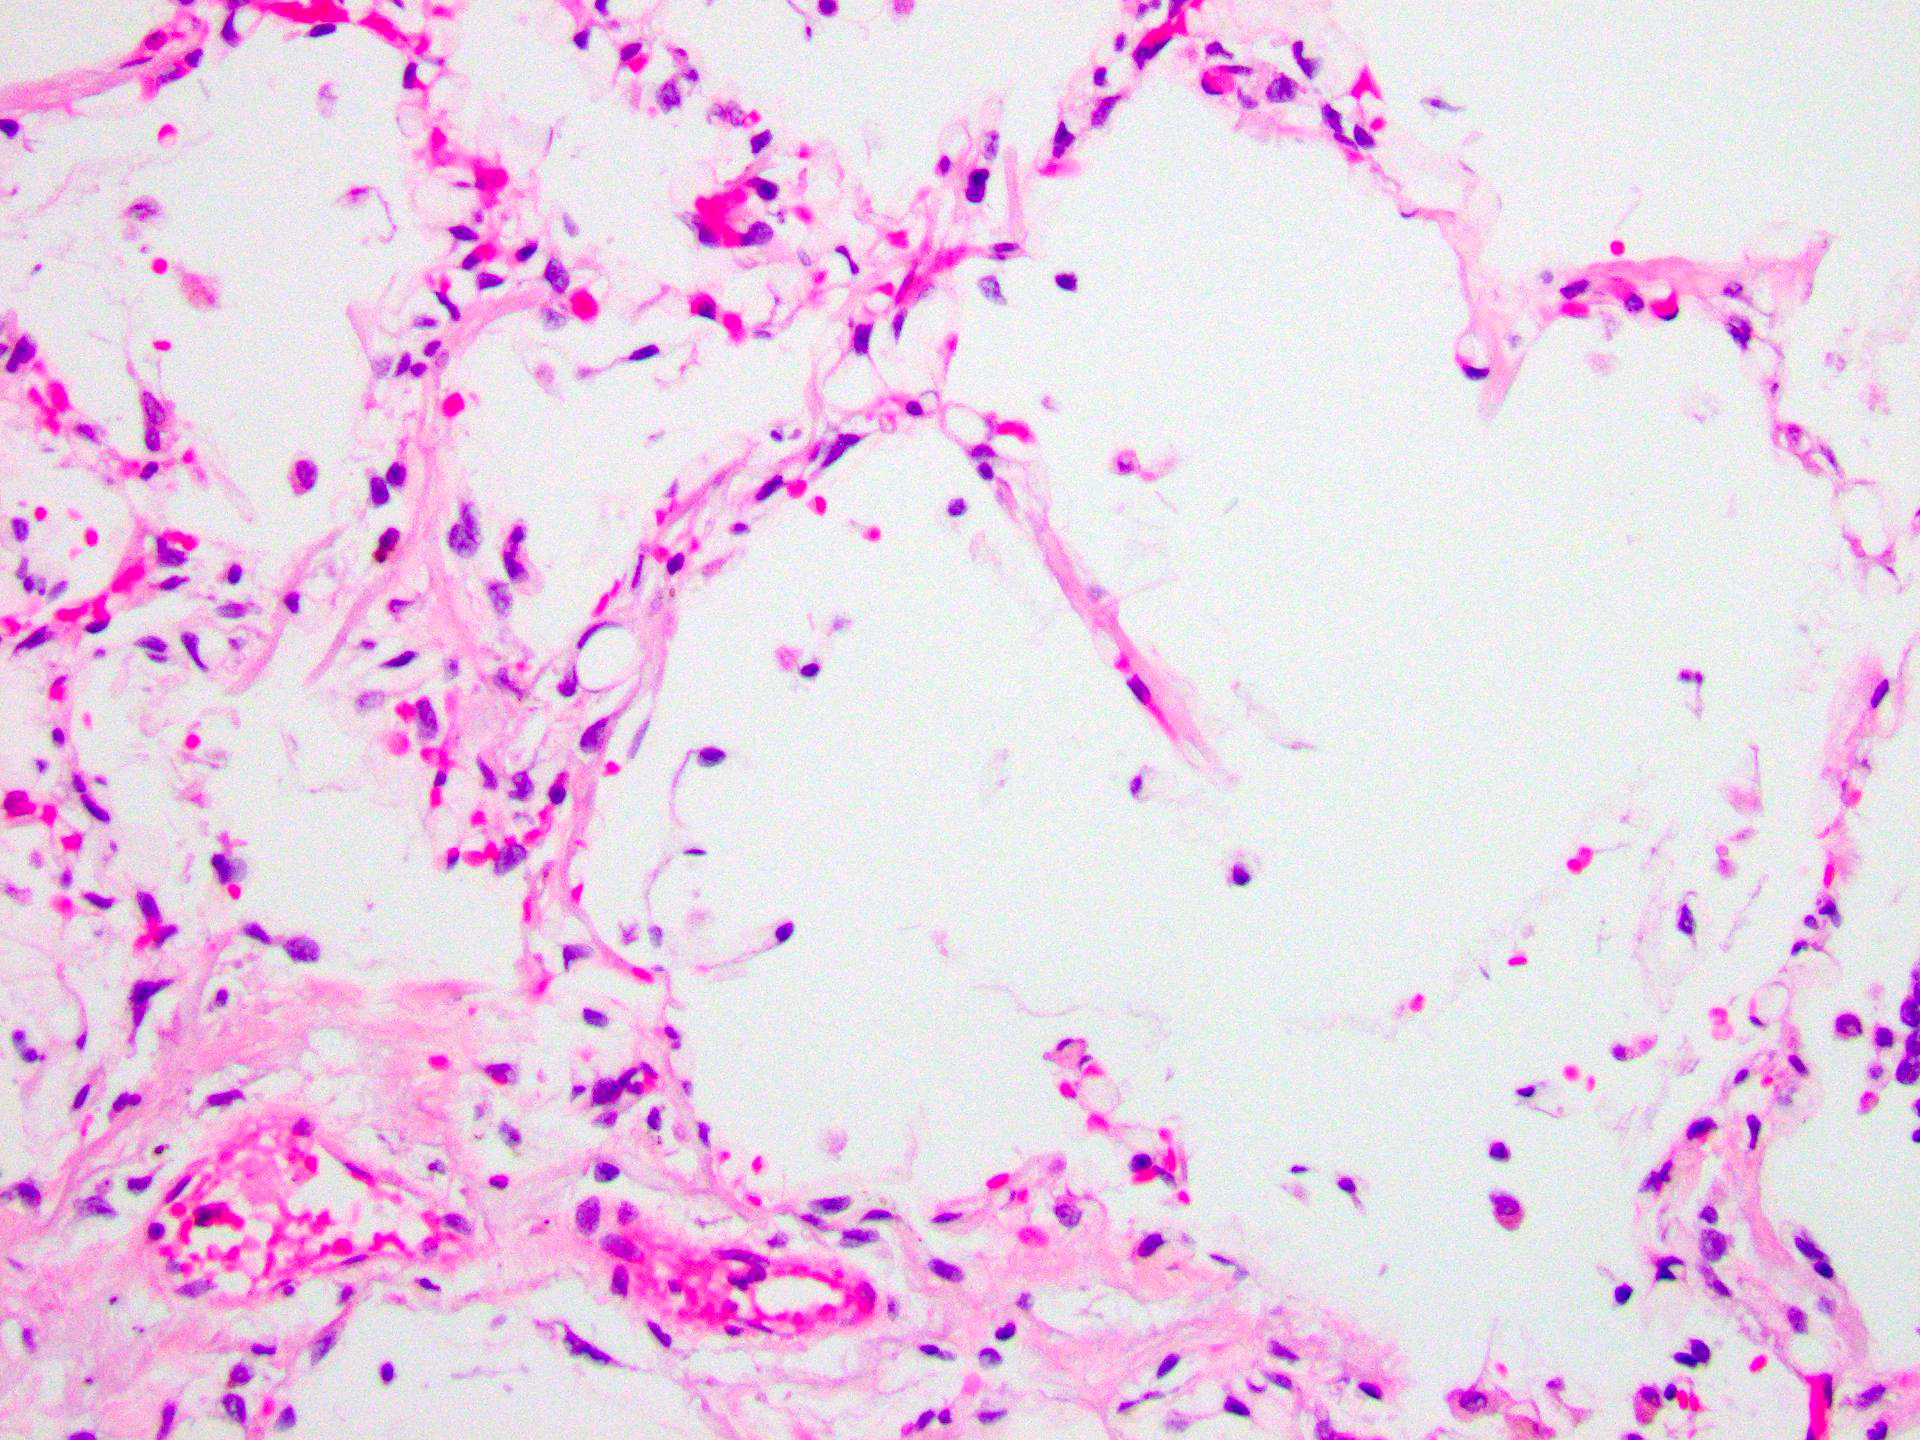

At time of postmortem examination, the lung revealed numerous round ‘empty spaces’ within the intra-alveolar septa (Figure 3). An Oil Red O stain of the lung positively highlighted these areas as consisting of fat (Figure 4). An Oil Red O stain of the kidney also demonstrated similar finding (Figure 5).